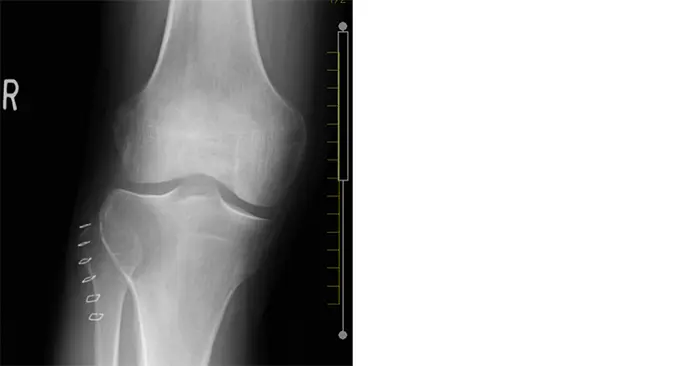

36歳男性.1ヶ月前から持続する右膝関節痛を主訴にA病院受診.X線画像では右脛骨近位部骨幹端から骨端に透亮像あり,MRI脂肪抑制で充実性腫瘍(T1低信号,T2およびDWIで高信号)が認められ,当院へ紹介受診となった.右脛骨近位端GCT(Campanacci grade Ⅱ)の臨床診断となり,転移は認められず,拡大掻爬術が施行された.

画像所見

受診時の膝関節X線画像では,右脛骨の骨幹端から骨端に及ぶ骨透亮像が認められ(Figure 1),単純CTで,同様に膨張性に発育する44x40x37mmの溶骨性病変が認められ,関節面まで1mm程度のところまで進展している.硬化縁はなく,内部は筋肉より低濃度で石灰化は認められない(Figure 2).また,右膝関節のMRIでも右脛骨近位外側,骨幹端から骨端線を越えて骨端まで及ぶ44×40×36mm大の病変を認める.内部はT1強調像で低信号,T2強調像で筋肉より高信号でほぼ均一.周囲に軽度の骨髄浮腫を伴い,拡散強調像では高信号を呈している.脂肪抑制T1強調像で高信号であるが,造影後との差分画像で全体が増強されている.以上の所見よりGCTが疑われる(Figure 3).